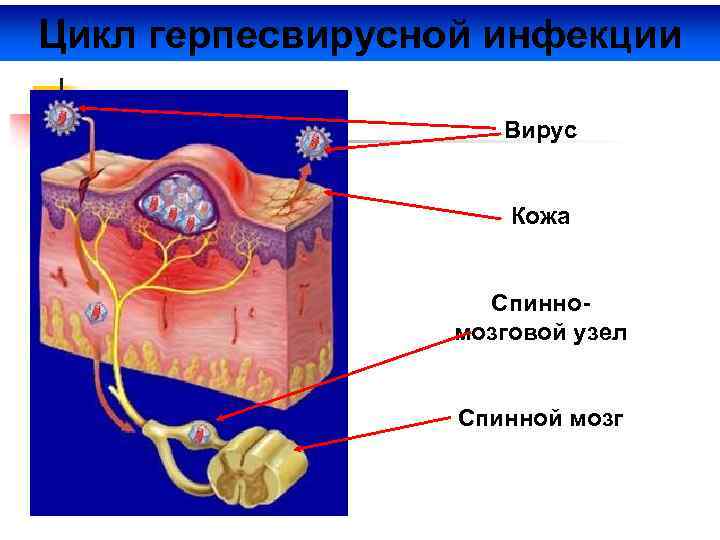

Цикл герпесвирусной инфекции Вирус Кожа Спинномозговой узел Спинной мозг

Цикл герпесвирусной инфекции Вирус Кожа Спинномозговой узел Спинной мозг